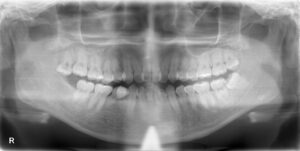

次の患者様は、画面向かって左上の親知らずです。

麻酔を行い、ものの30秒で抜歯できました(^^♪

【えっ、もう終わったんですか?】

これが処置を終えた際の患者様のお言葉です。

緊張なさっていましたが、処置後には痛みもなく満面の笑みでよかったとおっしゃっていました。